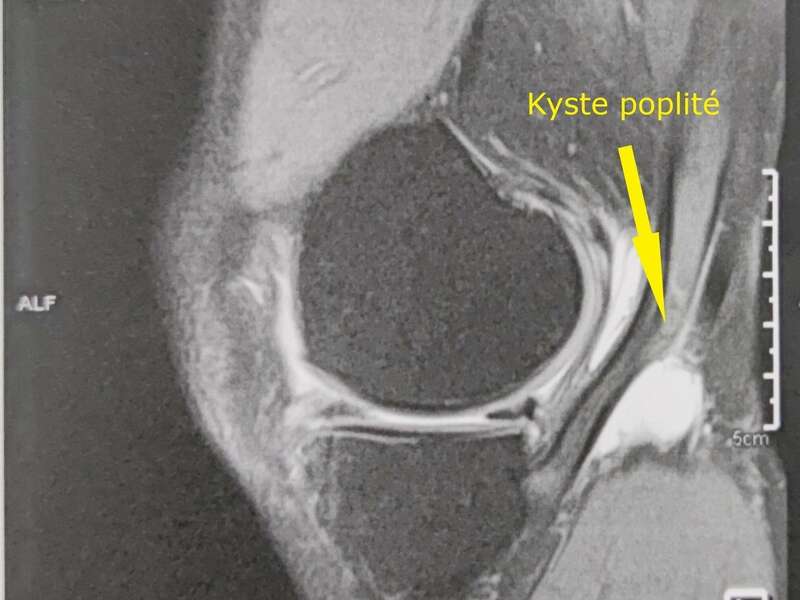

Le kyste poplité est la conséquence d’une fragilisation de la capsule articulaire postérieure en rapport avec une fissure méniscale horizontale. Lors d’un « agression » de votre genou, du liquide synovial est sécrété par votre genou. Du fait de l’augmentation de la pression liquidienne dans l’articulation, le liquide va avoir tendance à alimenter une bourse dans le creux poplité.

Le principal motif de consultation des fissures méniscales est la douleur du genou. Elle peut être plus ou moins intense et apparaitre subitement ou progressivement. L’interrogatoire étudie le mécanisme lésionnel et recherche d’éventuels facteurs de risque. L’examen clinique permet de localiser l’origine de vos douleurs, de rechercher un gonflement de votre genou, un kyste dans le creux poplité. Les manœuvres dynamiques recherchent un pseudo-blocage ou des douleurs à la compression du ménisque atteint.